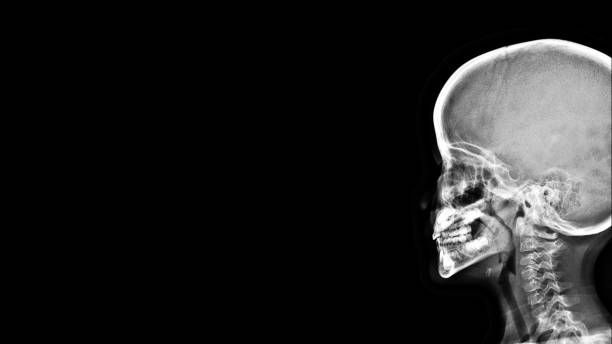

이비인후과에서 내시경 검사, 측면 두부 방사선(X-ray) 검사,

수면 상태 평가를 통해 비대된 아데노이드의 크기와 기능적 문제 여부를 평가합니다.